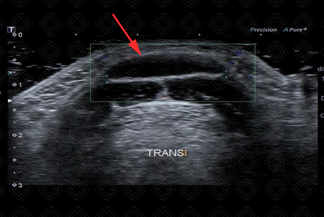

Texto alternativo para a imagem Figura 1. Créditos: Dra. Elazir Mota - Rio de Janeiro/RJ

Descrição das figuras 1 e 2: Ultrassonografia cervical. Lesão localizada na linha média da região cervical, com contornos bem definidos, anecoica, com reforço acústico posterior (seta vermelha). O osso hioide é uma referência anatômica importante e que deve ser descrito no laudo ultrassonográfico.

• Ultrassonografia cervical: Exame de escolha na avaliação dos cistos tireoglossos. A aparência ultrassonográfica é de uma lesão anecoica/hipoecoica, bem definida, com paredes finas, com reforço acústico posterior, na região cervical anterior, na linha média ou paramediana. A lesão pode ser hipoecoica devido a sangramento ou processo infeccioso associado. Em geral, não há vascularização ao color Doppler (figura 1);